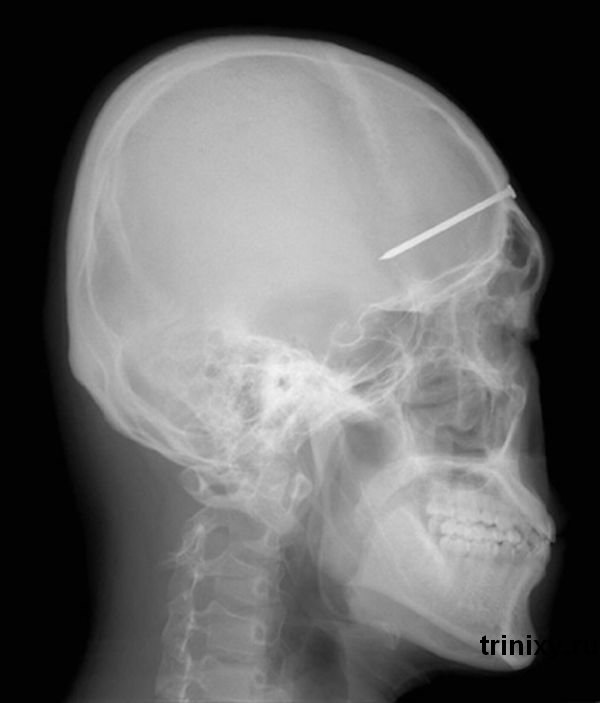

при рентгене у мамаши патология в норме

Цитата (взгрустняк @ 28.04.2012 - 13:22)

Или так. cool.gif